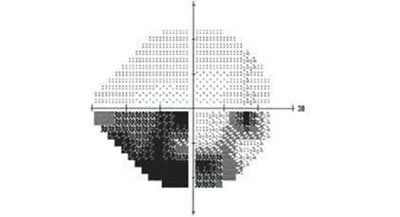

视野决定了眼睛能看到的范围,如果视野出现缺损(上图黑色部分),就说明眼睛在黑色部分里是看不见的。